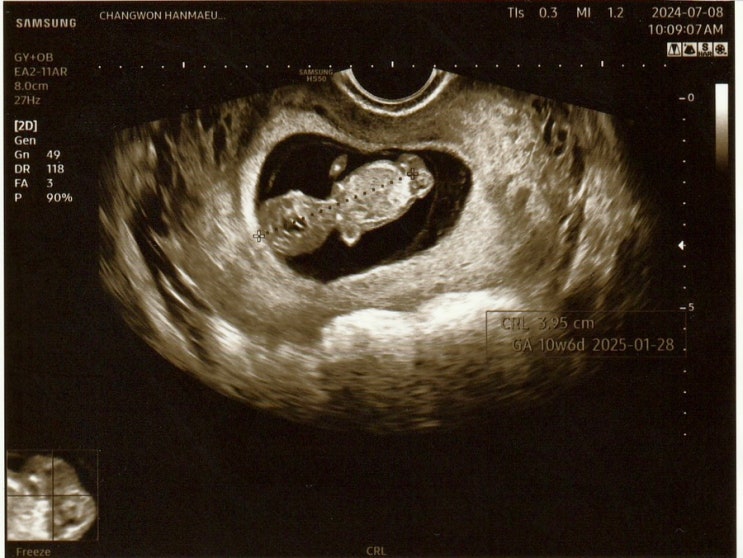

2024. 07. 08 (월) 8시 30분 채혈 9시 45분 진료 예약 10시 05분 진료 아침 진료+채혈이 있는 날은 대부분 ...